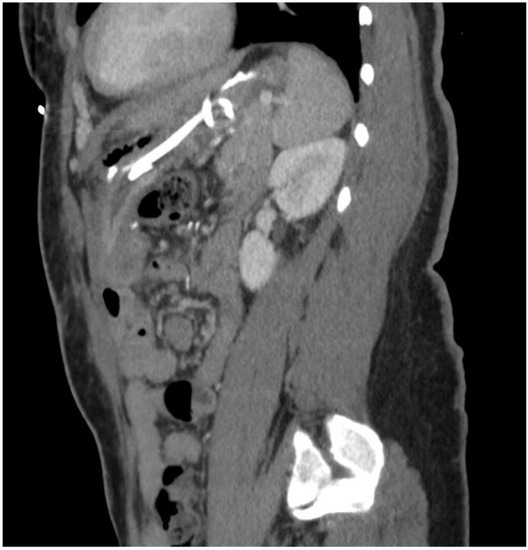

2. Detailed Case Description